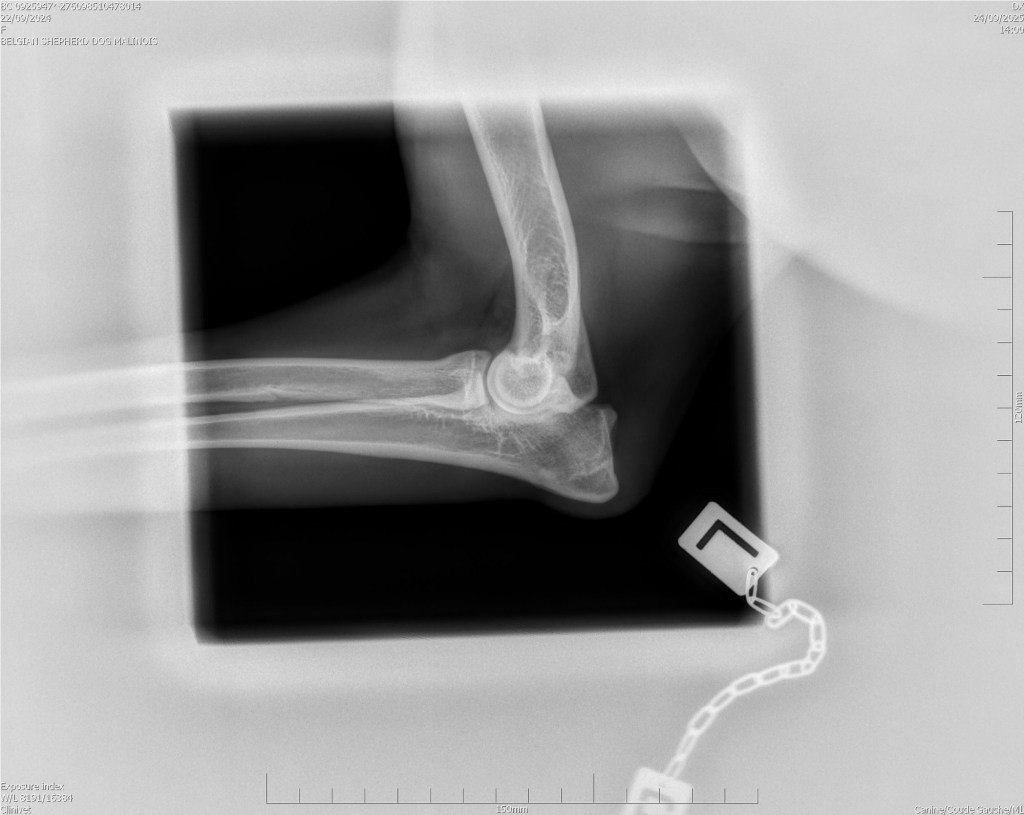

Hips 2/3

Elbows 0/0